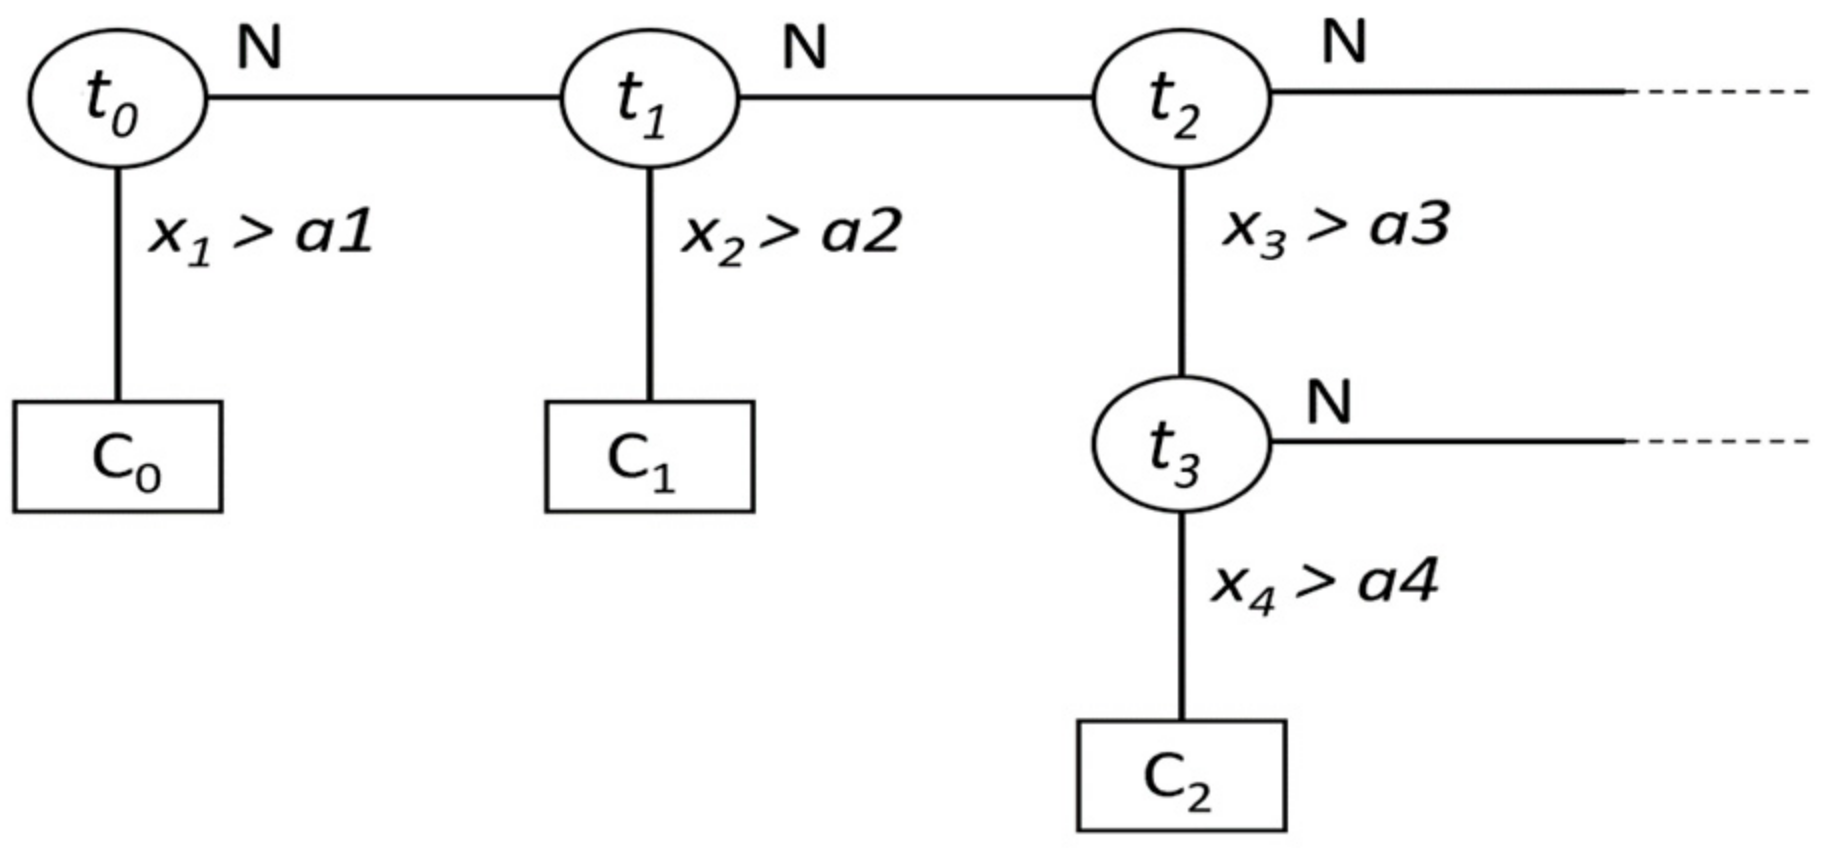

5.2.1. Fast Decision Tree (FDT)